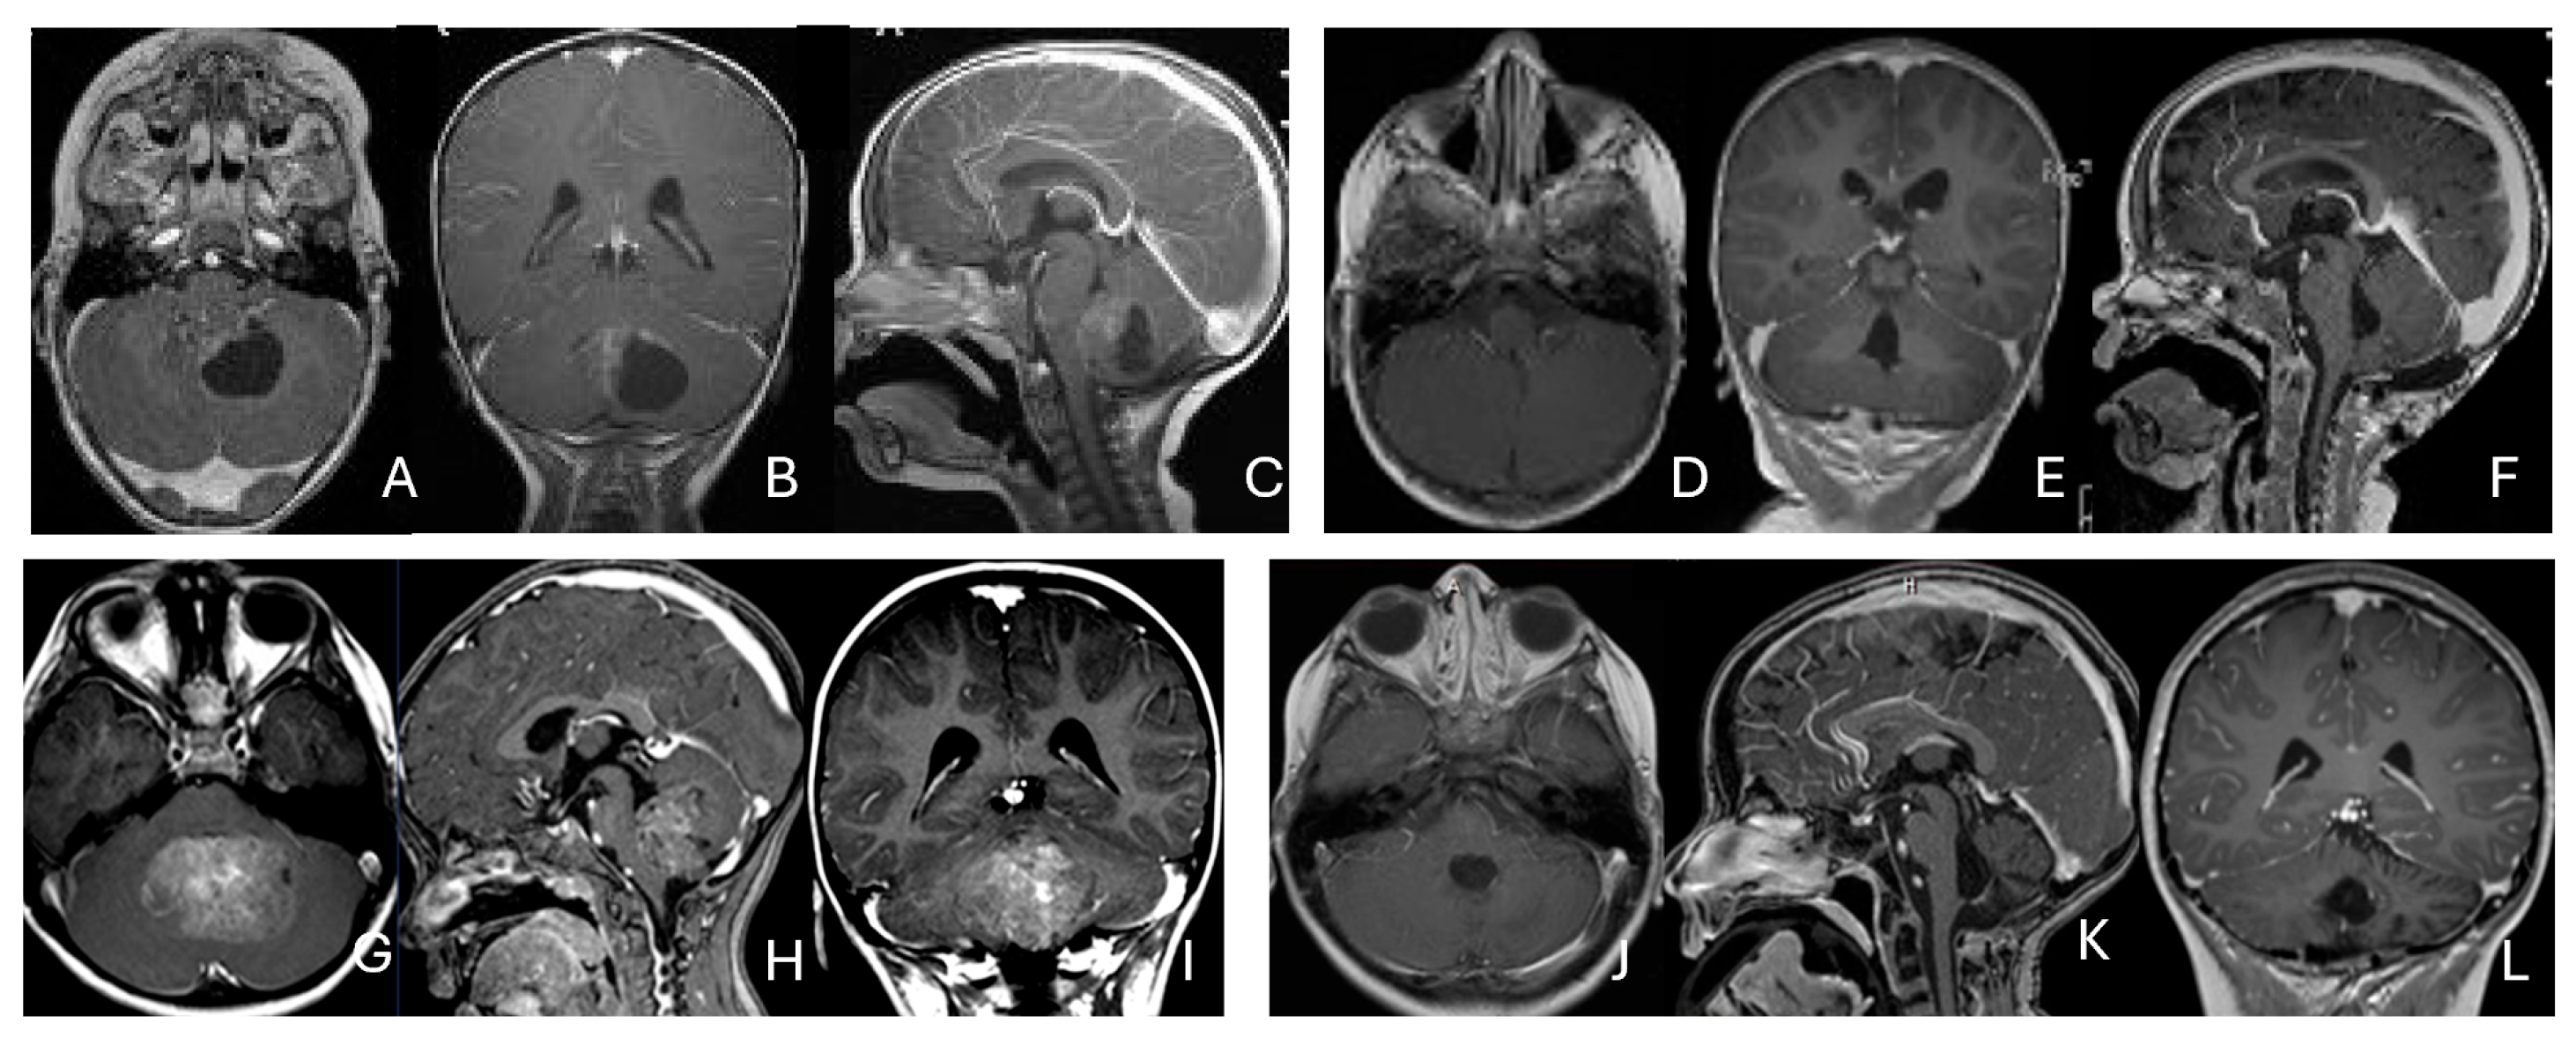

Five patients had tumors centered within the fourth ventricle; in four of these, the tumor involved the floor of the ventricle (brainstem) (Figure 7).

Figure 7.

Fourth ventricle ATRT. (A–F): MR images ((A), axial; (B), coronal; (C), sagittal) of a 21-month-old boy show a predominantly cystic fourth ventricular mass. The lesion appeared to arise from the inferior vermis, and the floor of the fourth ventricle was partially infiltrated. Postoperative images ((D), axial; (E), coronal; (F), sagittal) demonstrate gross-total resection. (G–L): MR images ((G), axial; (H), sagittal; (I), coronal) of a 3.5-year-old girl reveal a solid fourth ventricular tumor with heterogeneous enhancement. The floor of the fourth ventricle was intact, and the lesion appeared to originate from the inferior vermis. Postoperative images ((J), axial; (K), sagittal; (L), coronal) confirm gross-total resection.

In five additional patients, tumors straddled both the fourth ventricle, the lateral recess and in some further the CPA and/or the cerebellomedullary fissure (CMF), producing a dumbbell-shaped configuration (Figure 8).

Figure 8.

Fourth ventricle-lateral recess/CMFOK ATRT. (A–E): MR images ((A), axial; (B), coronal; (C), sagittal) of a 12-month-old boy show a fourth ventricular ATRT extending to the CMF through the lateral recess and with multiple peritumoral cysts. A partial invasion to the pons was noted at surgery. Postoperative images ((D), axial; (E), sagittal) demonstrate gross-total resection. Fourth ventricle-CPA ATRT. (F–J): MRI ((F): axial T2-weighted; (G): post-contrast coronal; (H): post-contrast sagittal) of a 5-month-old girl reveal a heterogeneous, dumbbell-shaped ATRT extending from the fourth ventricle into the CPA/CMF. During surgery, invasion of the lateral wall of the medulla oblongata was observed, and a subtotal resection was achieved. Post-contrast MRI ((I): axial; (J): sagittal) reveals residual enhancing tumor at the CMF.

Eight patients had lesions localized to the CPA/CMF region (Figure 9). Among them, two had concurrent bilateral lesions. In one bilateral case, the lesions were asymmetric with questionable evidence of spinal cerebrospinal fluid dissemination, whereas another patient exhibited symmetric bilateral lesions.

Figure 9.

Cerebellopontine angle (CPA) ATRT. (A–E): T2-weighted MR images ((A), axial; (B), coronal) of a 7-week-old girl show a massive ATRT centered in the right CPA/CMF. Postoperative MR images ((C), axial; (D), coronal) show a gross-total resection of a highly vascular, necrotic mass. Intraoperative photograph following tumor resection illustrates key landmarks: LR, lateral recess; V, trigeminal nerve; VII/VIII, facial and vestibulocochlear nerves; IX/X, glossopharyngeal and vagus nerves. The cranial nerves were free of tumor. ATRT appeared to originate from the lateral posterior cerebellar lobe. (F–K): MR images ((F), axial; (G), axial) of a 3.5-year-old girl show bilateral CPA tumors: a larger, partially cystic mass on the left (open arrow) and a smaller solid mass extending toward Meckel’s cave on the right (solid arrow). The left-sided tumor was resected via a retrosigmoid approach ((H), axial; (I), axial). The lesion arose from the lateral cerebellar hemisphere and extended into the CPA cistern without cranial nerve invasion. Following chemoradiotherapy, the right-sided lesion resolved ((J), axial; (K), axial).

None of the CPA ATRTs showed evidence of cranial nerve origin at the time of surgical inspection (Figure 9E).